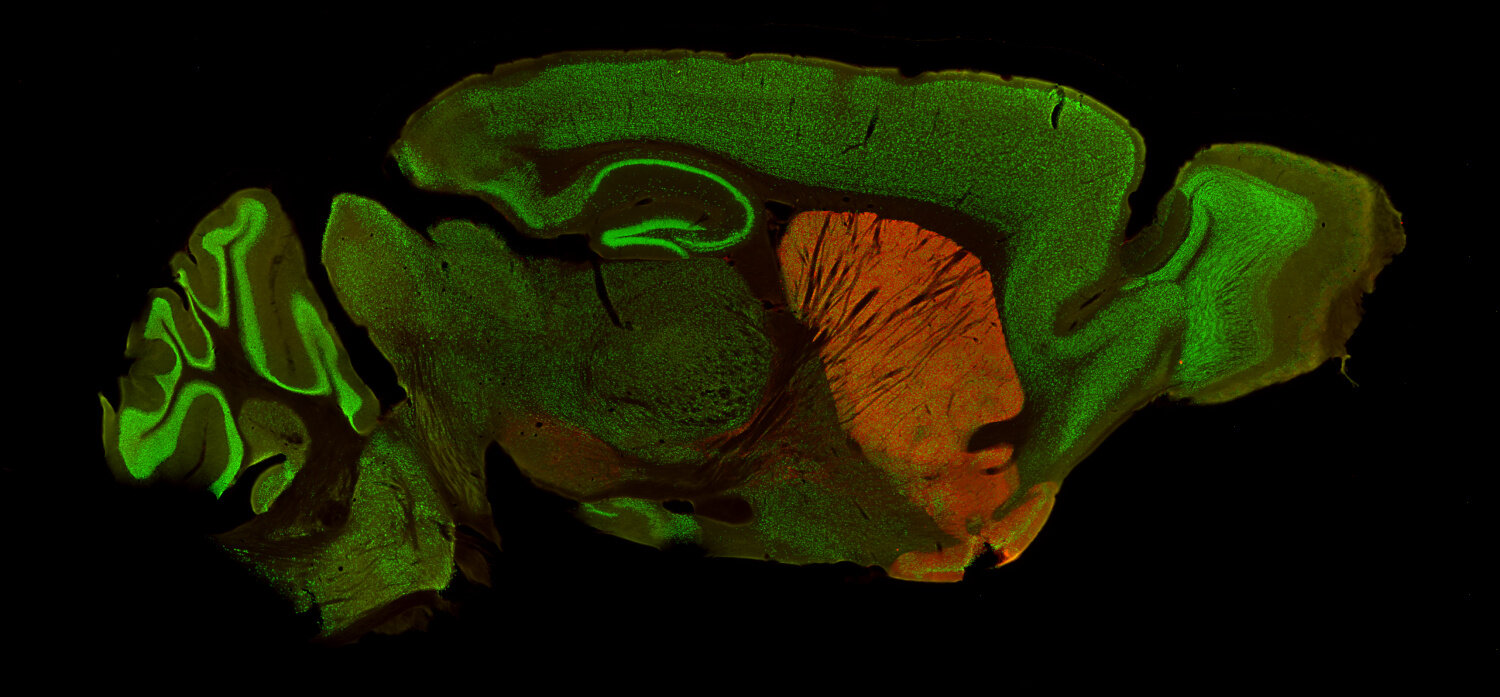

IHC: 1 : 500 gallery

Immunohistochemistry (IHC) on 4% PFA perfusion fixed tissue with 24h PFA post fixation. Immunoreactivity is usually revealed by fluorescence or a chromogenic substrate. Some antibodies require special fixation methods or antigen retrieval steps. For details, please refer to the ”Remarks” section.

Functionally, DAT contributes to the termination of DA signaling by reuptaking DA, thereby controlling both the duration and magnitude of dopaminergic transmission (4). It is predominantly found in dopaminergic neurons and enriched in regions such as the striatum, substantia nigra, and ventral tegmental area, which are associated with motor control and reward mechanisms (5).

For more information on protein expression pattern, please refer to the overview image in our SYSY Antibodies ATLAS.